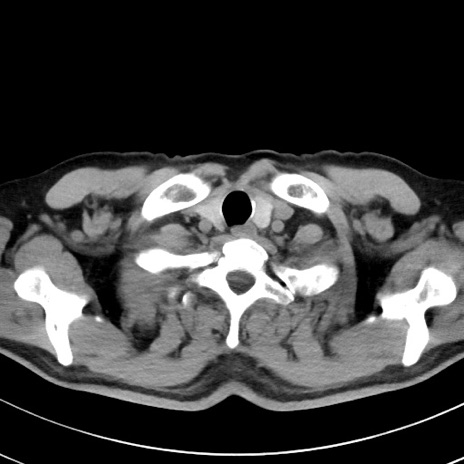

【腹部TIPS】症例29 参考症例 CT(横断像)

症例

70歳代男性